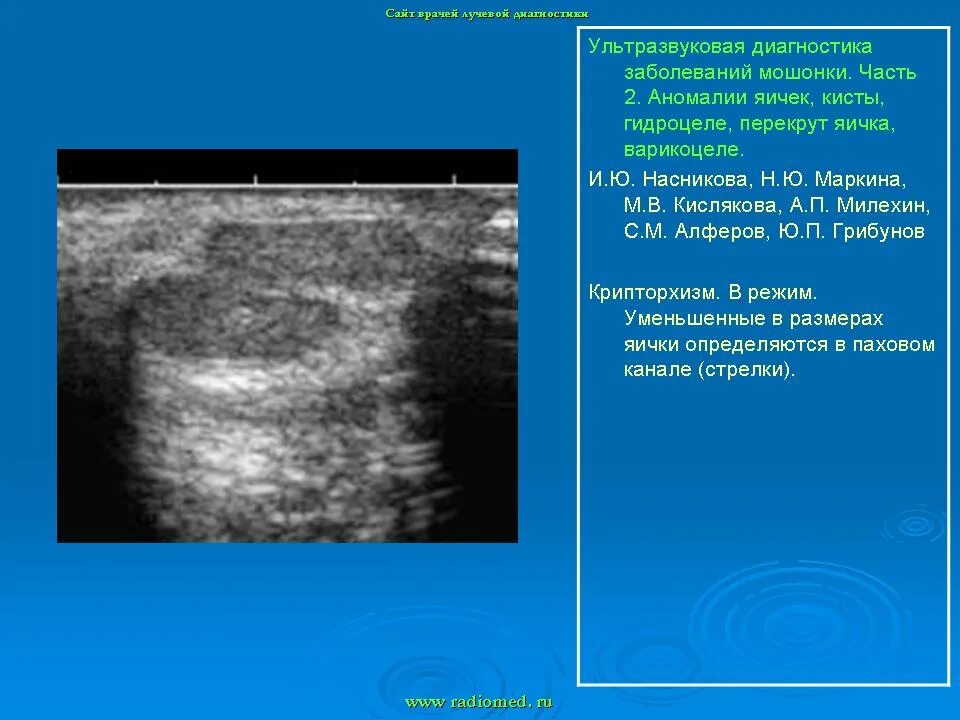

Диффузные изменения яичек